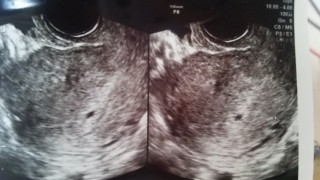

4日前に胎嚢確認しましたが、茶色のおりものが出て心配になり、受診。胎嚢も大きくなっていて前回10.5mm→16.1mmに!胎芽も見えました!(3.7mm)胎嚢が大きくなる際に出血することがあるということでした。子宮の上の方にいるし、茶色やピンク色の出血はほぼ大丈夫なので、とりあえず安心して良いとのこと。来週心拍確認できますように☆

去年の夏に流産後、7ヶ月経ってまた赤ちゃんがお腹に来てくれました。 初診のエコーではドキドキしましたが、胎嚢と心拍が確認出来てとりあえず安心。これからも元気に育ってね!母子手帳交付が待ち遠しいです。